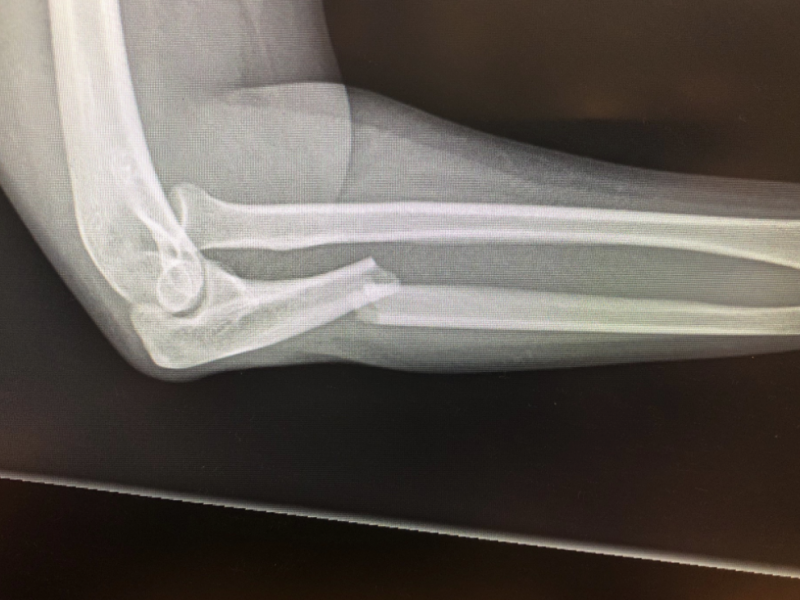

A 23 yo female presents after a motor vehicle collision with